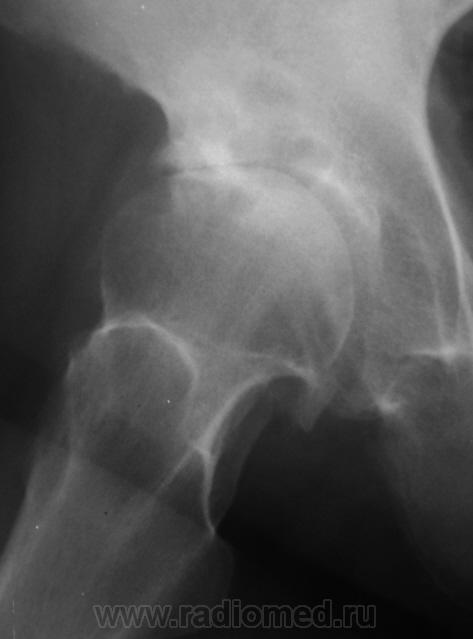

Пол пациента: Мужской пол Тип патологии: Другое Область исследования: Скелетно-мышечная система Методы исследования: Rg Пациент направлен на рентгенографию тазобедренного сустава. https://radiomed.ru/sites/default/files/styles/case_slider_image/public/user/12/2.p2100008.jpg?itok=xeIOIPjU https://radiomed.ru/sites/default/files/styles/case_slider_image/public/user/12/3.p2100008a.jpg?itok=-f8UPzuU ID:12067 Втр, 15/02/2011 - 20:09 #1 Фаина Не на сайте Был на сайте: 2 года 11 месяцев назад Зарегистрирован: 14.12.2008 - 16:51 Публикации: 323 Деф.артроз с кистовидной перестройкой, хотя может эти простветления за счет асептического некроза Втр, 15/02/2011 - 22:49 #2 Петрович Не на сайте Был на сайте: 7 лет 3 месяцев назад Зарегистрирован: 22.03.2009 - 01:13 Публикации: 3908 ДДПКП. Но всё же нужна и прямая проекция Неоднозначно всё Втр, 15/02/2011 - 23:50 #3 Fujimi Не на сайте Был на сайте: 12 лет 6 месяцев назад Зарегистрирован: 20.01.2011 - 23:08 Публикации: 259 Петрович wrote: ДДПКП... Не могли бы Вы расшифровать? Ср, 16/02/2011 - 00:05 #4 Петрович Не на сайте Был на сайте: 7 лет 3 месяцев назад Зарегистрирован: 22.03.2009 - 01:13 Публикации: 3908 ДДПКП = Дегенеративно-дистрофическое поражение с кистовидной перестройкой. Одно из трёх дегенеративно-дистрофических поражений, выделяемых/описанных Н.С. Косинской. Могу дать почитать её Классический труд. Неоднозначно всё Ср, 16/02/2011 - 00:12 #5 Fujimi Не на сайте Был на сайте: 12 лет 6 месяцев назад Зарегистрирован: 20.01.2011 - 23:08 Публикации: 259 Спасибо. У меня есть. Так можно писать в заключении? Ср, 16/02/2011 - 00:14 #6 Петрович Не на сайте Был на сайте: 7 лет 3 месяцев назад Зарегистрирован: 22.03.2009 - 01:13 Публикации: 3908 Я пишу. С указанием стадии. Неоднозначно всё Ср, 16/02/2011 - 00:17 #7 Fujimi Не на сайте Был на сайте: 12 лет 6 месяцев назад Зарегистрирован: 20.01.2011 - 23:08 Публикации: 259 Большое Вам спасибо! Пт, 18/02/2011 - 22:00 #8 Катенёв Валенти... Не на сайте Был на сайте: 7 лет 1 месяц назад Зарегистрирован: 22.03.2008 - 22:15 Публикации: 54876 Спасибо за высказанные мнения. Сб, 19/02/2011 - 10:12 #9 Евгений1313 Не на сайте Был на сайте: 13 лет 2 недели назад Зарегистрирован: 15.10.2010 - 19:13 Публикации: 808 Так то оно так ,да только кистозная перестройка чаше поражает головку, а здесь она интактная.И напротив-ограниченный участок деструкции в области "крыши" вертлужной впадины.Я думаю что это метастаз в ости впадины. Сб, 19/02/2011 - 18:39 #10 Петрович Не на сайте Был на сайте: 7 лет 3 месяцев назад Зарегистрирован: 22.03.2009 - 01:13 Публикации: 3908 Для суждения об интактности головки всё же необходима прямая проекция. Метастаз если есть, то не один. И миеломная не исключается вовсе. Неоднозначно всё

Деф.артроз с кистовидной перестройкой, хотя может эти простветления за счет асептического некроза

ДДПКП. Но всё же нужна и прямая проекция

Так то оно так ,да только кистозная перестройка чаше поражает головку, а здесь она интактная.И напротив-ограниченный участок деструкции в области "крыши" вертлужной впадины.Я думаю что это метастаз в ости впадины.

Для суждения об интактности головки всё же необходима прямая проекция. Метастаз если есть, то не один. И миеломная не исключается вовсе.